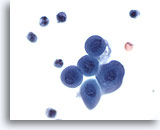

Miction, résultat négatif

La miction représente le moyen le rapide plus rapide d’obtenir un échantillon d’urine.

20x